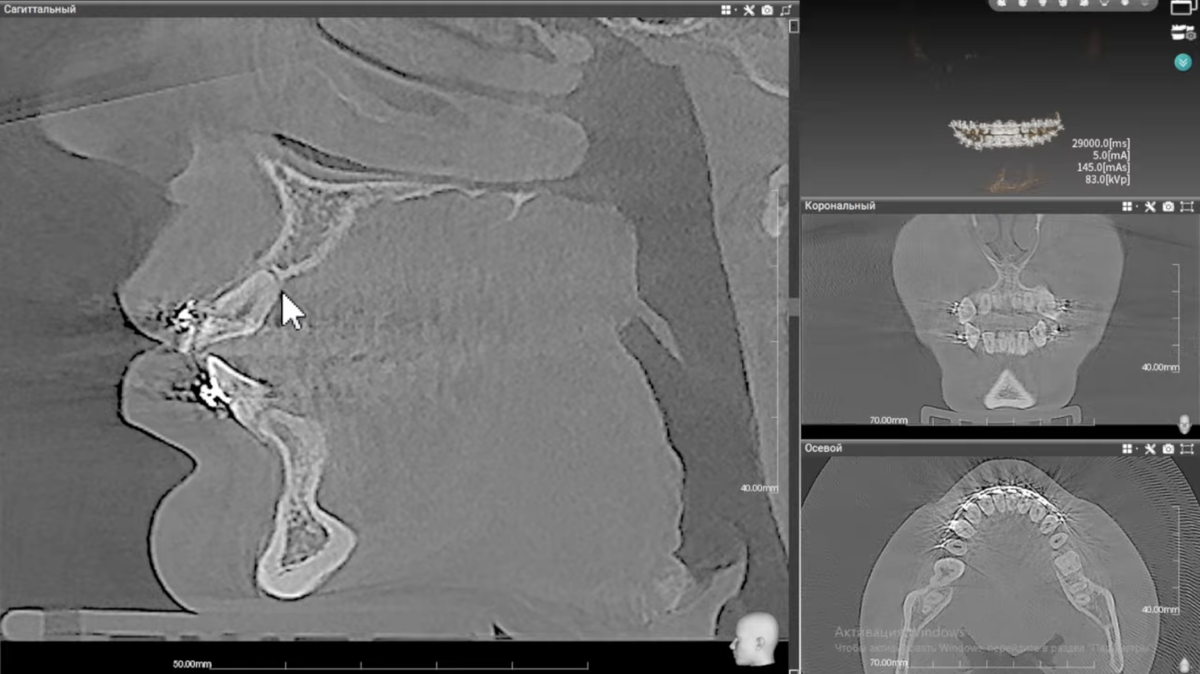

На компьютерной томографии мы увидели следующее: корни четырех верхних резцов укоротились практически в три раза.

Но на контрольной КТ стало видно: примерно треть длины корня резцов была утрачена.

КТ до начала лечения

КТ под конец лечения

Причина — значительная дистализация. При перемещении зуб уперся в плотную кортикальную пластинку. Вместо того чтобы рассосалась кость, частично рассосался корень. Это необратимо.